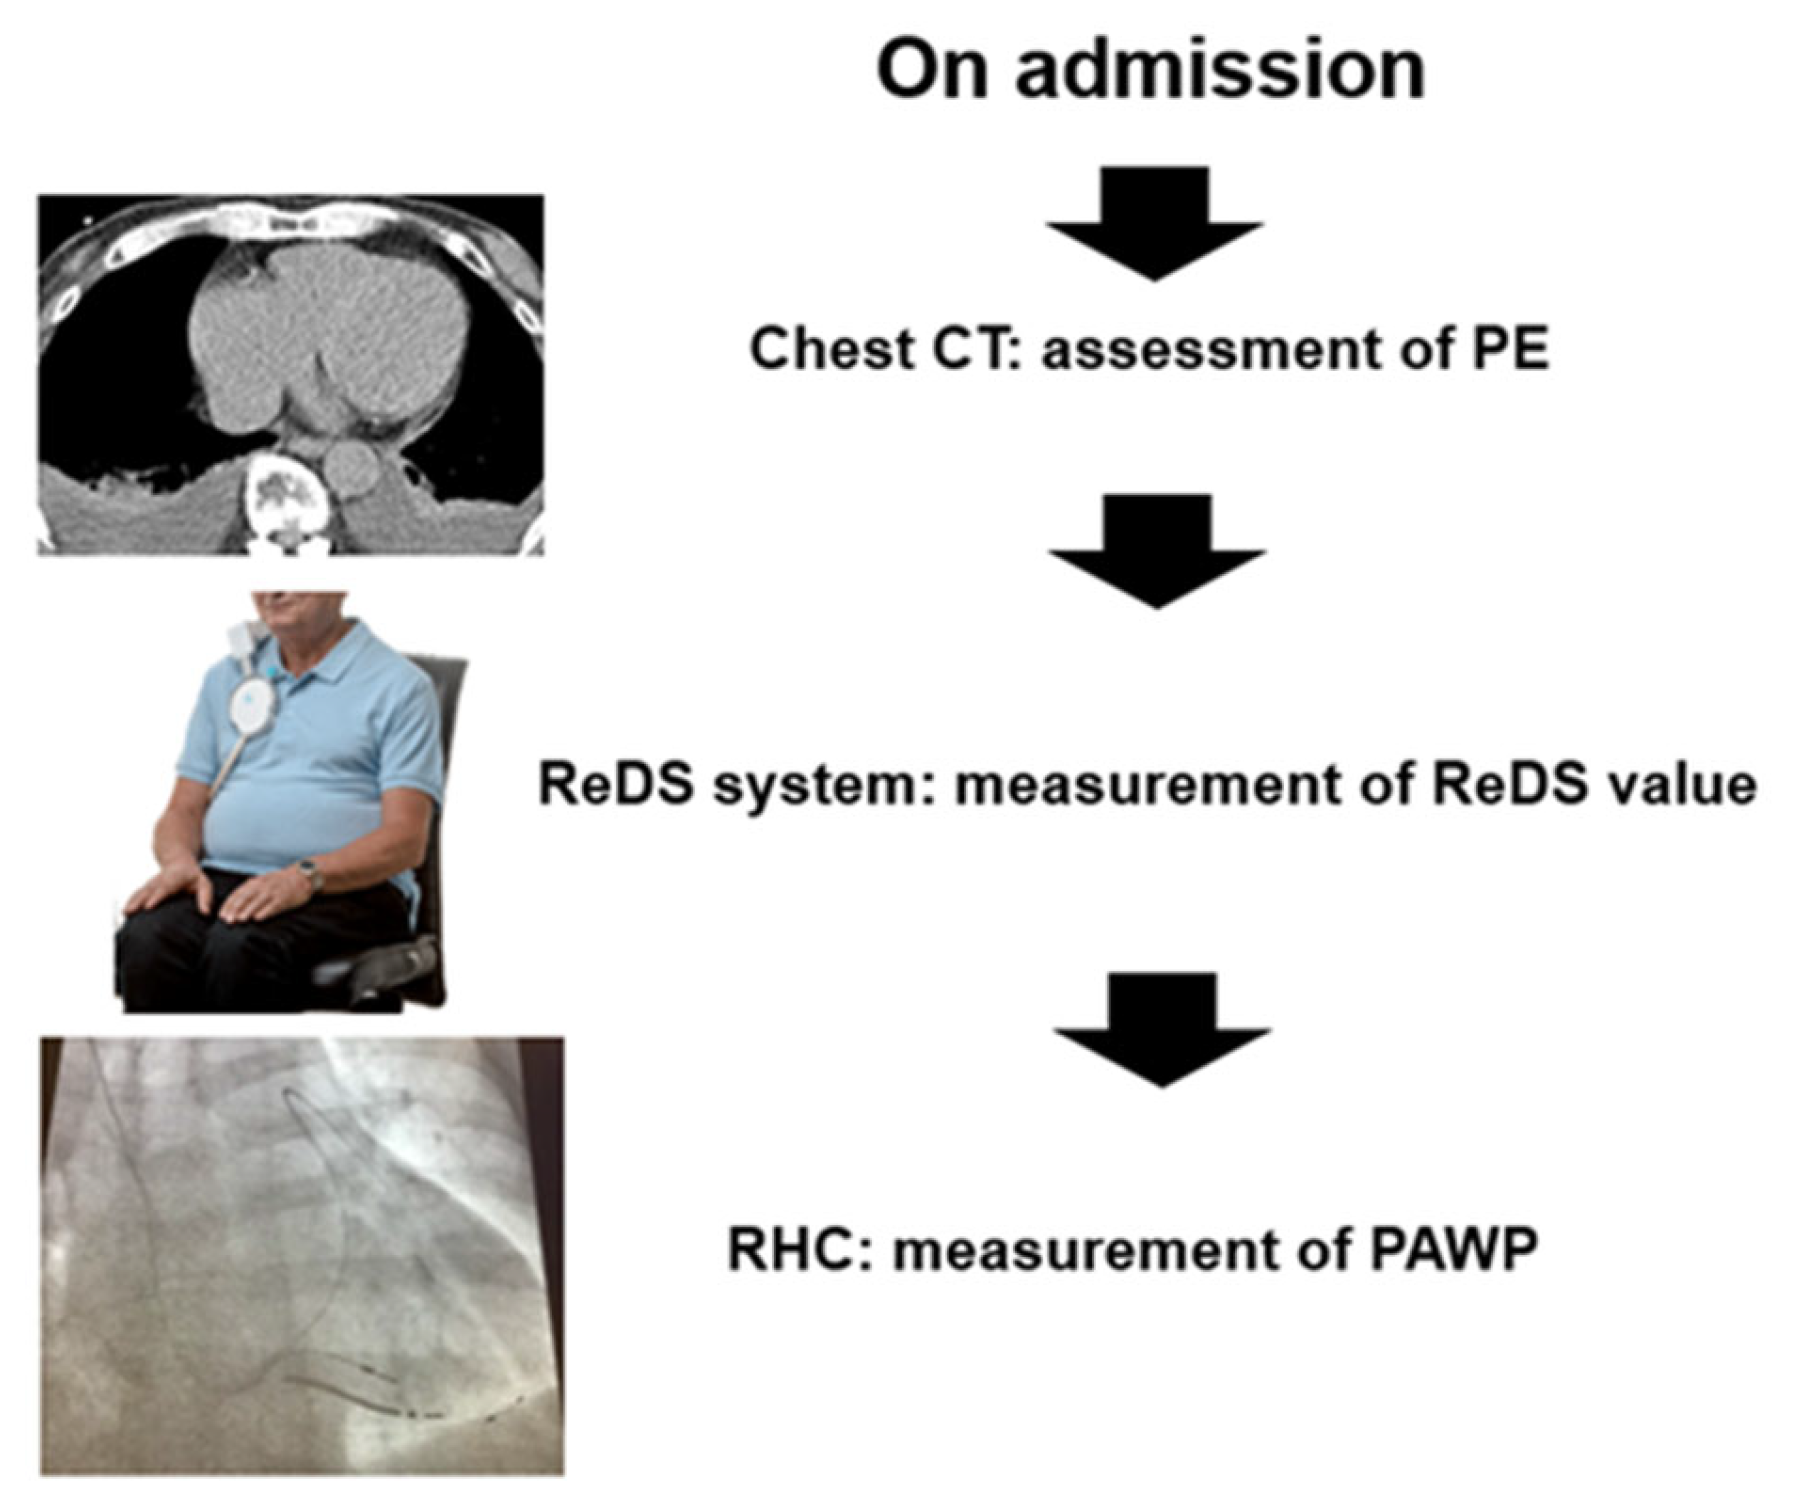

2. Methods

2.1. Study Design

2.3. ReDS Measurement

2.4. Right Heart Catheterization

2.5. Chest Computed Tomography